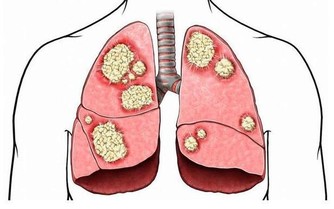

下肢動脈硬化閉塞症小腿抽筋頻繁,還要警惕血管性疾病可能,尤其是老年人。下肢血管硬化時,管腔會變窄,導致局部供血不足、血液循環不暢,組織缺氧及代謝產物蓄積,會使得肢體末端因為缺血出現抽筋、疼痛等不適。如果治療不及時,血管狹窄會逐漸加重,甚至引起外周器官營養缺乏,嚴重時發生壞疽等不良後果。